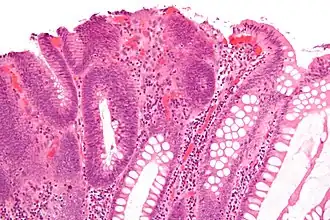

Microvesicular hyperplastic polyp. H&E stain. -

| Tubular adenoma | 2% at 1.5 cm[12] | Low to high grade dysplasia[13] | Over 75% of volume has tubular appearance.[14] |

| Hyperplastic polyp | 0% | No dysplasia.[10]